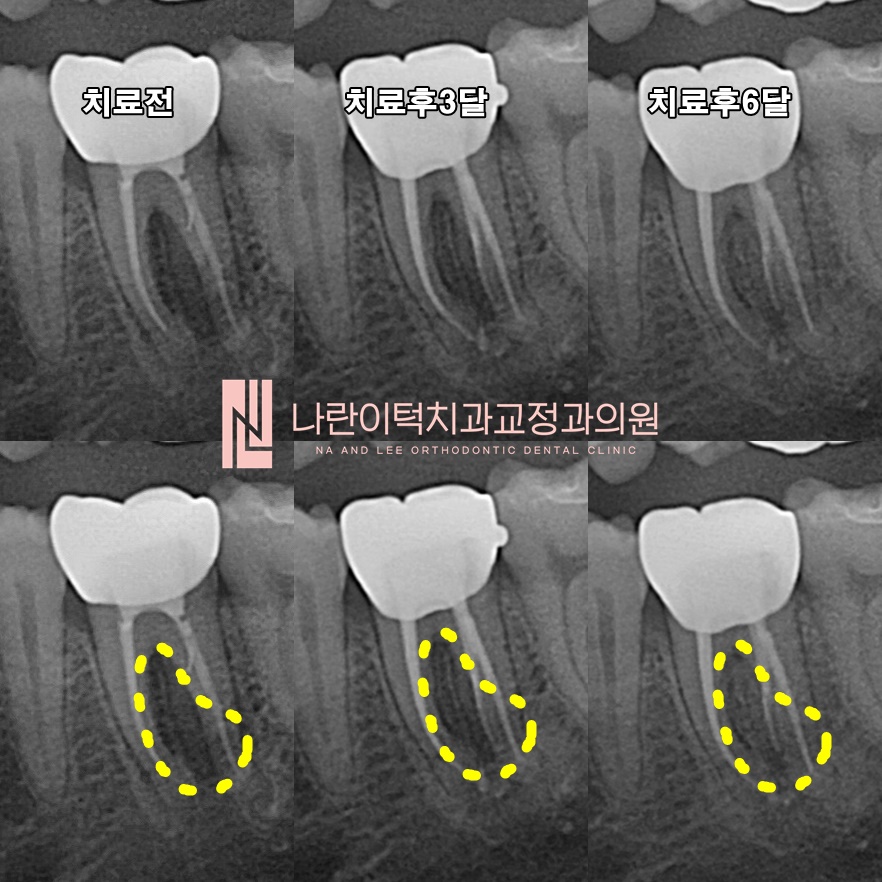

[염증 경과 Follow-up for PAR]

저작시 통증은 2주만에 금방 사라졌으나, 그렇다고 안심할 수 없습니다!

뿌리끝 염증(엑스레이상 검은 음영, 노란점선)이 점점 더 좋아지는지는 추가적인 추적관찰이 필요합니다.

크라운 임시합착 상태로 3개월 뒤 염증이 많이 좋아지고 뼈가 차는(엑스레이상 하얗게) 양상이 확인되면 크라운은 최종으로 합착합니다.

최종합착 후 3개월 뒤(재신경치료 후 6개월)까지도 추적관찰을 꼼꼼하게 진행하니, 기존뼈와 구분이 되지 않을 정도로 뼈가 완전히 차올랐습니다!

[전후비교 Before & After]

치료전후 비교!

#36치아의 다리 사이 검은 음영이 완전히 없어지고 튼튼한 뼈가 차올랐습니다!